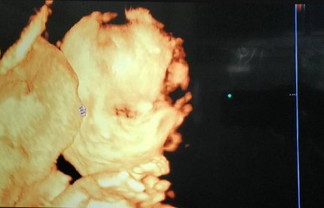

เด็กอายุครรภ์ 22สัปดาห์

อยู่ในเกณฑ์ดีมากลูก